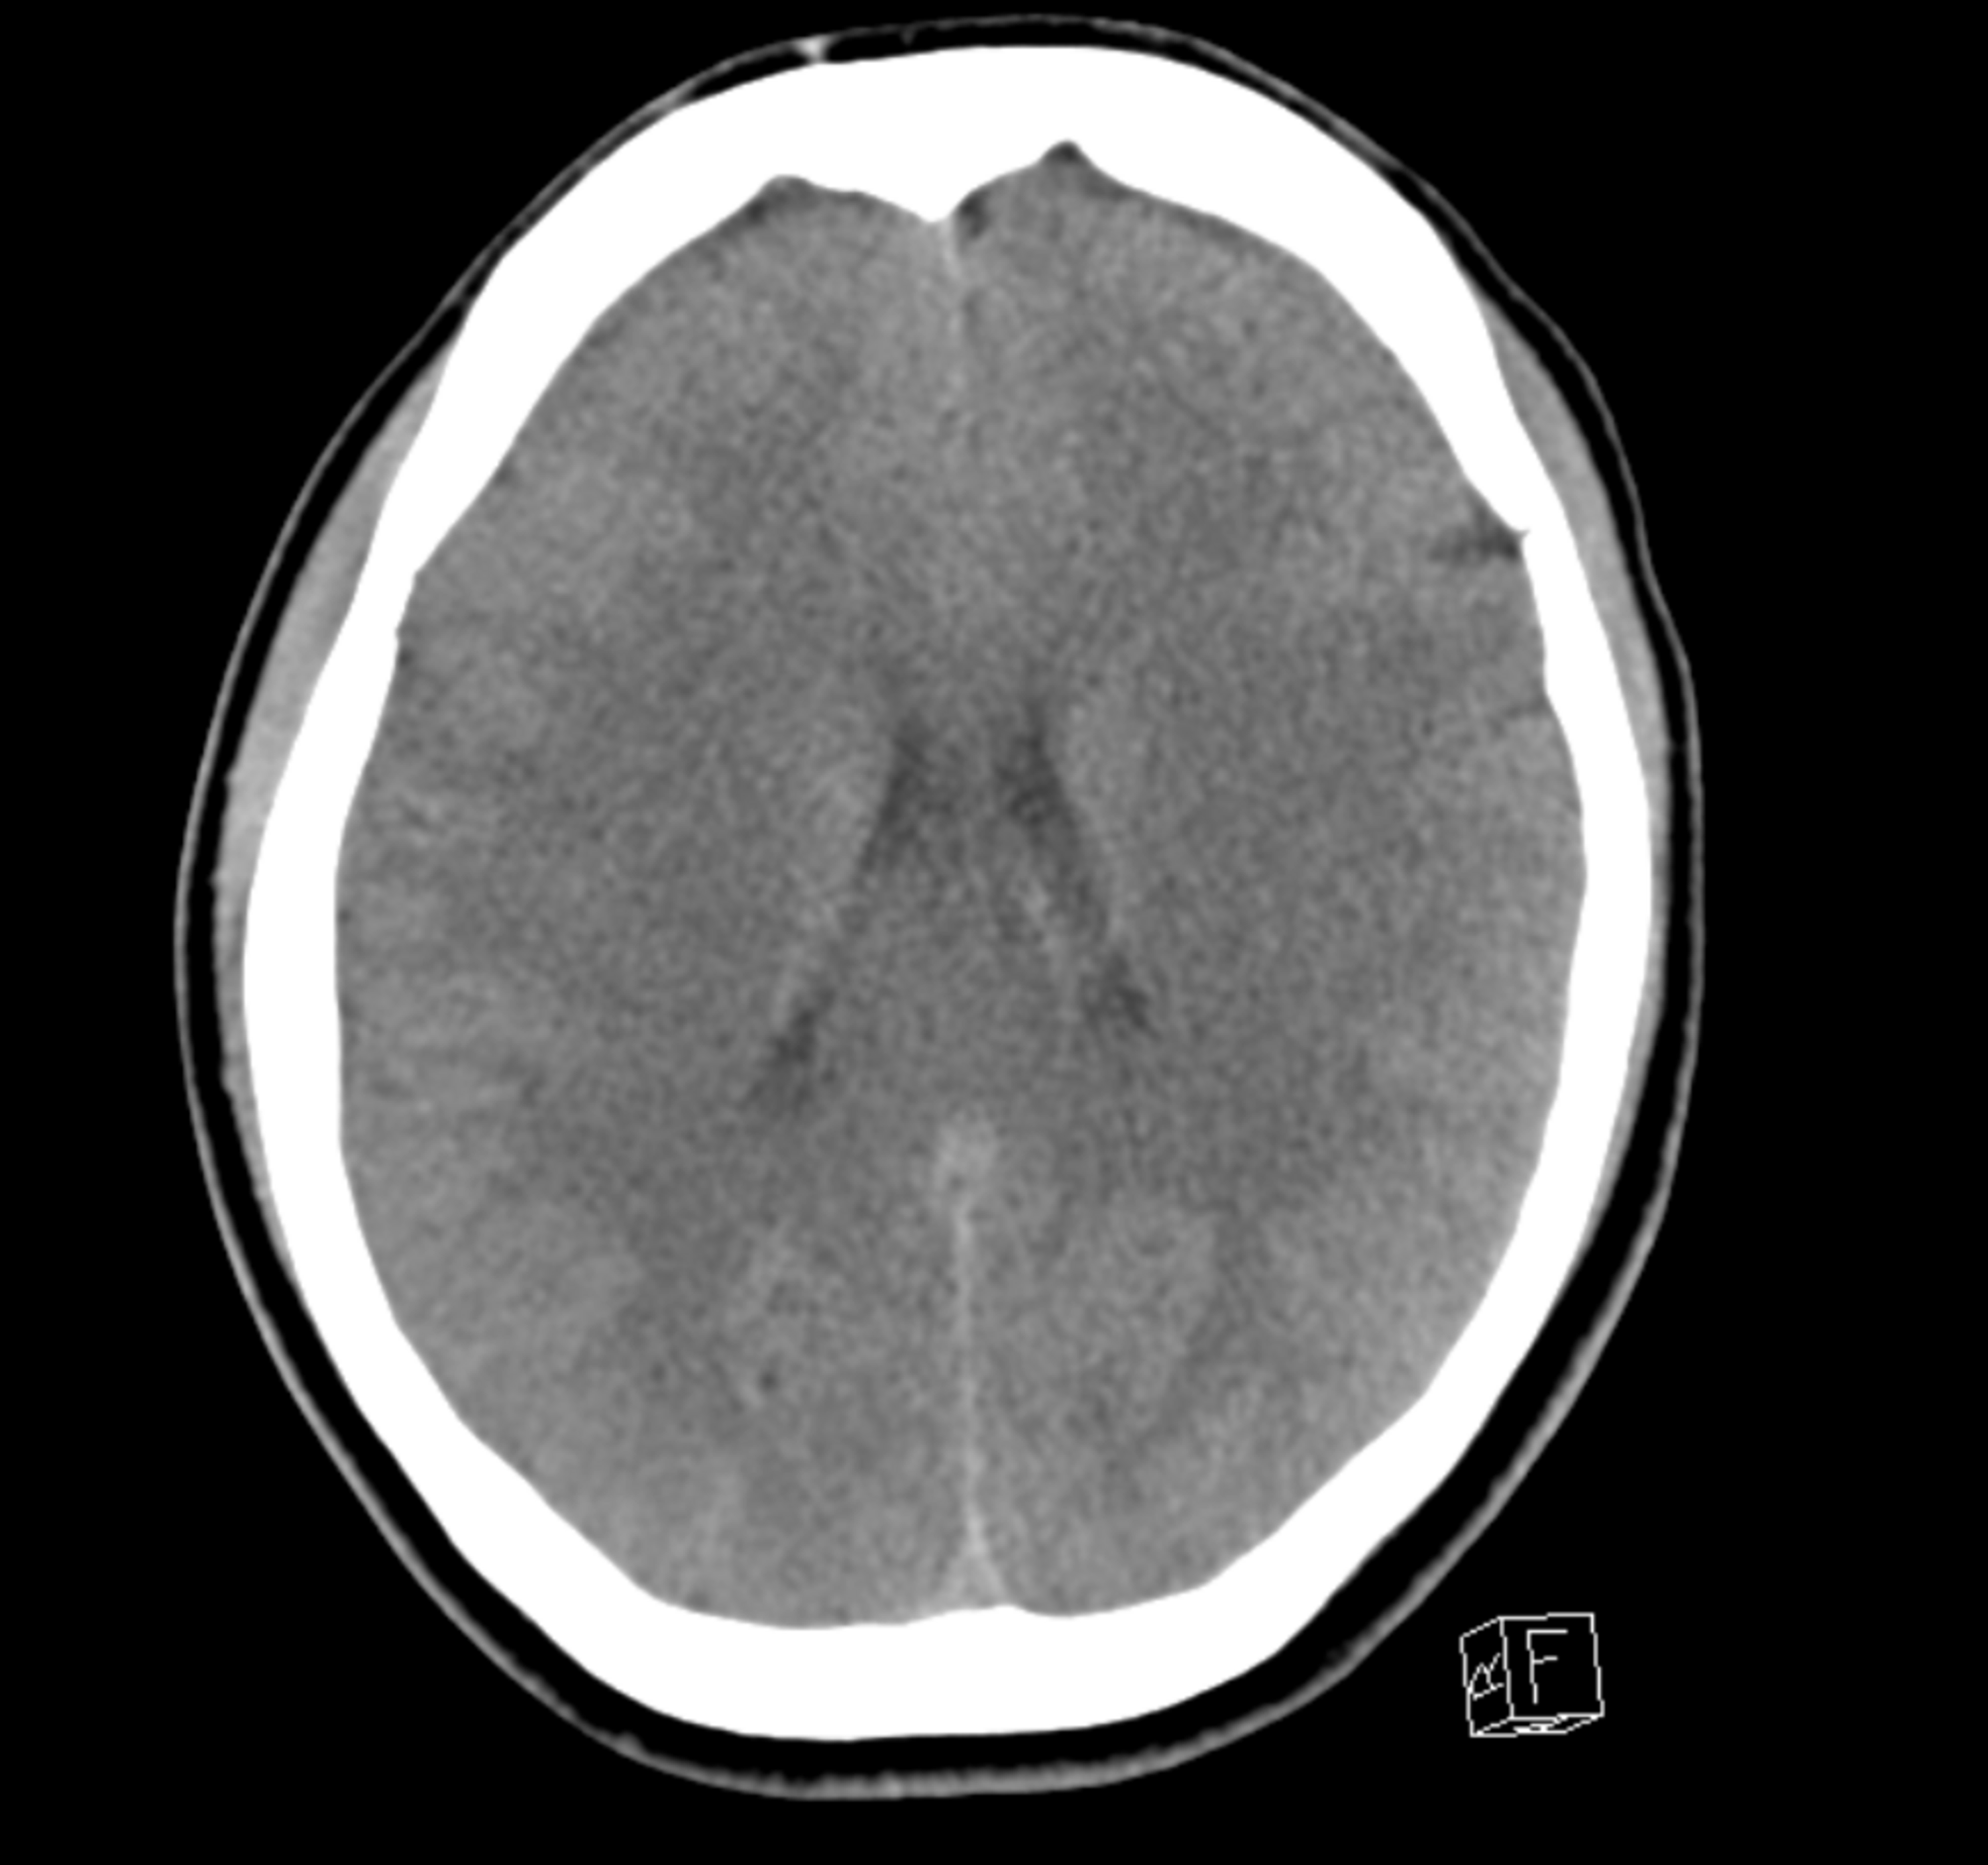

Melanie c armitage, rebecca j. A case of extrapontine myelinolysis confirmed by characteristic mri findings following an episode of extreme hyponatremia caused by psychogenic polydipsia is described involving a. Management of hyponatremia starts by establishing whether severe symptoms are present.